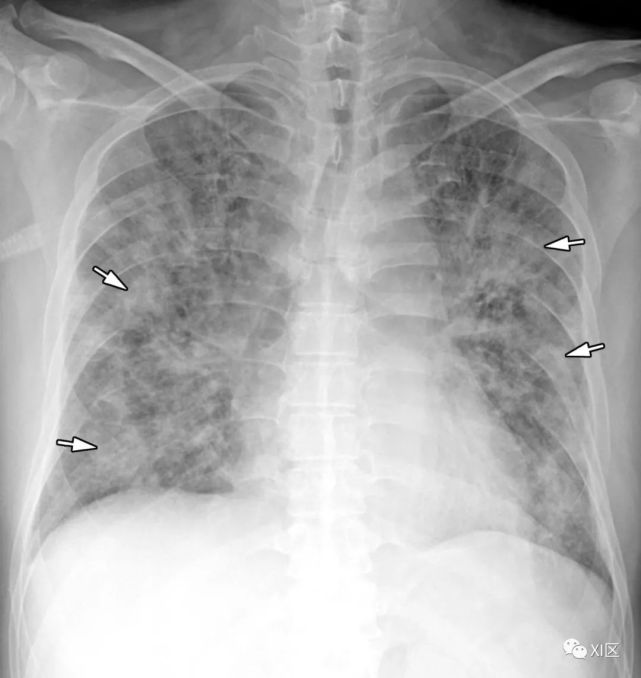

图8 20岁男子因腺病毒感染引起肺炎,伴有发热、咳嗽和呼吸困难。

(上) 最初的胸片显示左中下肺和右下肺区有不明确的斑片状实变和GGO(箭头)。同一天在叶间支气管水平(中)和肺下静脉水平(下)上获得的轴位胸部CT图像(厚度为5mm)显示不明确的斑片状GGO(箭头)和大叶实变(箭)。

Koo H J , Lim S , Choe J , et al. Radiographic and CT Features of Viral Pneumonia[J]. Radiographics, 2018, 38(3):719-739.